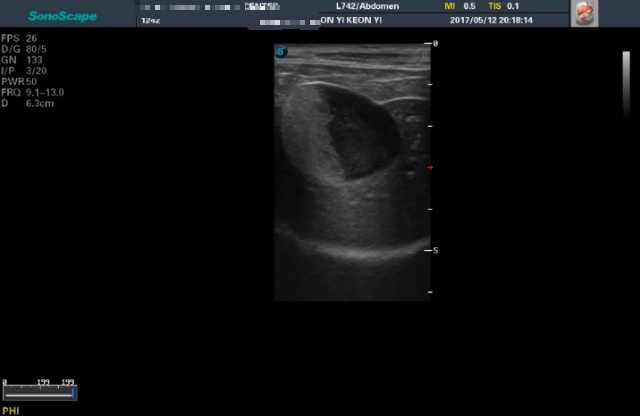

<5월12일 재검> 이땐 텅빈 반쪽이나마 너무 기뻤었어요...

<7월28일> 다시 원점..도로아미타불입니다. 다시봐도 속상하네요 (근데 이게 담낭이 맞긴 한건가..급혼란..)